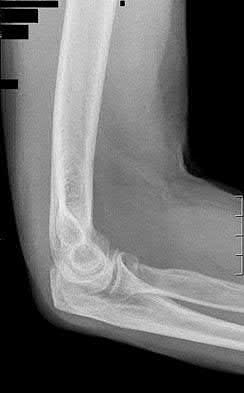

1012) A 54-year-old woman sustains the injury seen in Figures 71a and 71b. The injury involves her nondominant extremity. What should the patient be told regarding her expected outcome?

Corrent answer: 3

This is a Bado type 2 (posterior) Monteggia lesion, which is associated with higher rates of complications than other types of Monteggia lesions. The injury is associated with indirect high-energy trauma and less often pathologic causes. Of the four types of Monteggia lesions, the type 2 or posterior type is associated with the worst prognosis. These injuries are best treated surgically with dorsal plating of the ulna and reduction with fixation or arthroplasty of the radial head. The major complications seen with this injury pattern are nonunion and plate failure. Almost all patients have some loss of elbow range of motion. Satisfactory results based on functional scores for this injury are not universal. Neurologic injury and ulnohumeral instability are unusual with this type of injury. Full functional recovery is not expected with nonsurgical management.